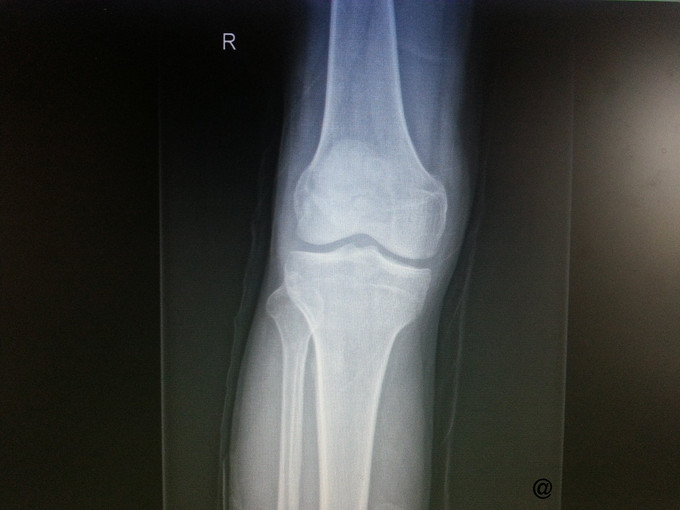

主诉:外伤致右膝疼痛、肿胀伴活动受限4小时 病史:患者四小时前骑车时不慎摔倒,右膝着地后出现疼痛,局部肿胀,压痛明显,右膝关节活动明显受限,皮肤稍有破损,无明显畸形,无瘀点瘀斑,右踝部及右脚趾活动正常。至我院急诊诊断:右髌骨骨折。为进一步治疗拟“右髌骨骨折”收治入院。 病程中患者神清,精神可,体温正常,胃纳夜眠可,二便无殊,体重无变化。

查体:右膝压痛明显,稍有肿胀,皮肤破损,无淤血斑块,主动被动活动受限;远端足背动脉可及搏动,右下肢远端、右踝、脚趾活动、感觉及皮温与左健侧基本相同。 辅检:X片提示右髌骨骨折。

诊断:右髌骨骨折 处理:右髌骨骨折切开复位克氏针内固定术